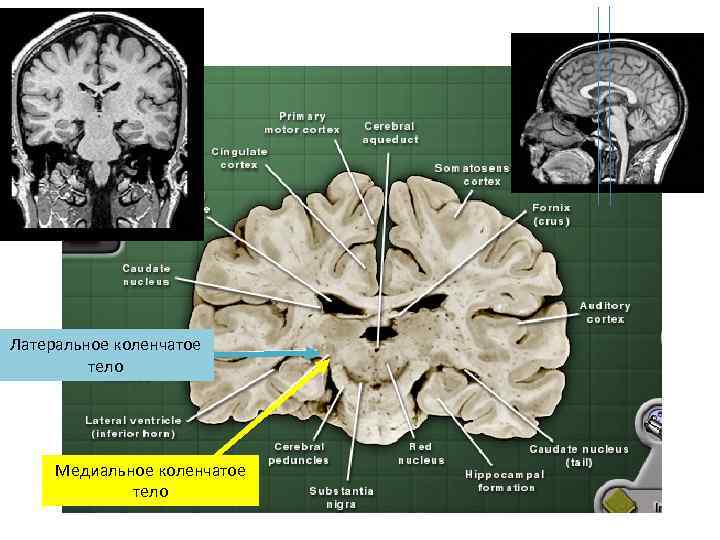

Задание 2. На двух фронтальных анатомических срезах на уровне промежуточного мозга, разметить ядра таламуса Задание 2. На двух фронтальных анатомических срезах на уровне промежуточного мозга, разметить ядра таламуса (см. схему и таблицу ядер таламуса). Отметить уровни фронтальных срезов на срединной сагиттальной МР томограмме. Подобрать МРТ срезы. Подушка Латеральное коленчатое тело Медиальное коленчатое тело медиальное дорсальное ядро таламуса (MD) Вентральное переднее и латеральное ядра таламуса (VA, VL) Третий желудочек

Латеральное коленчатое тело Медиальное коленчатое тело Латеральное коленчатое тело Медиальное коленчатое тело

Медиальное дорсальное ядро Вентролатеральная группа ядер Медиальное дорсальное ядро Вентролатеральная группа ядер